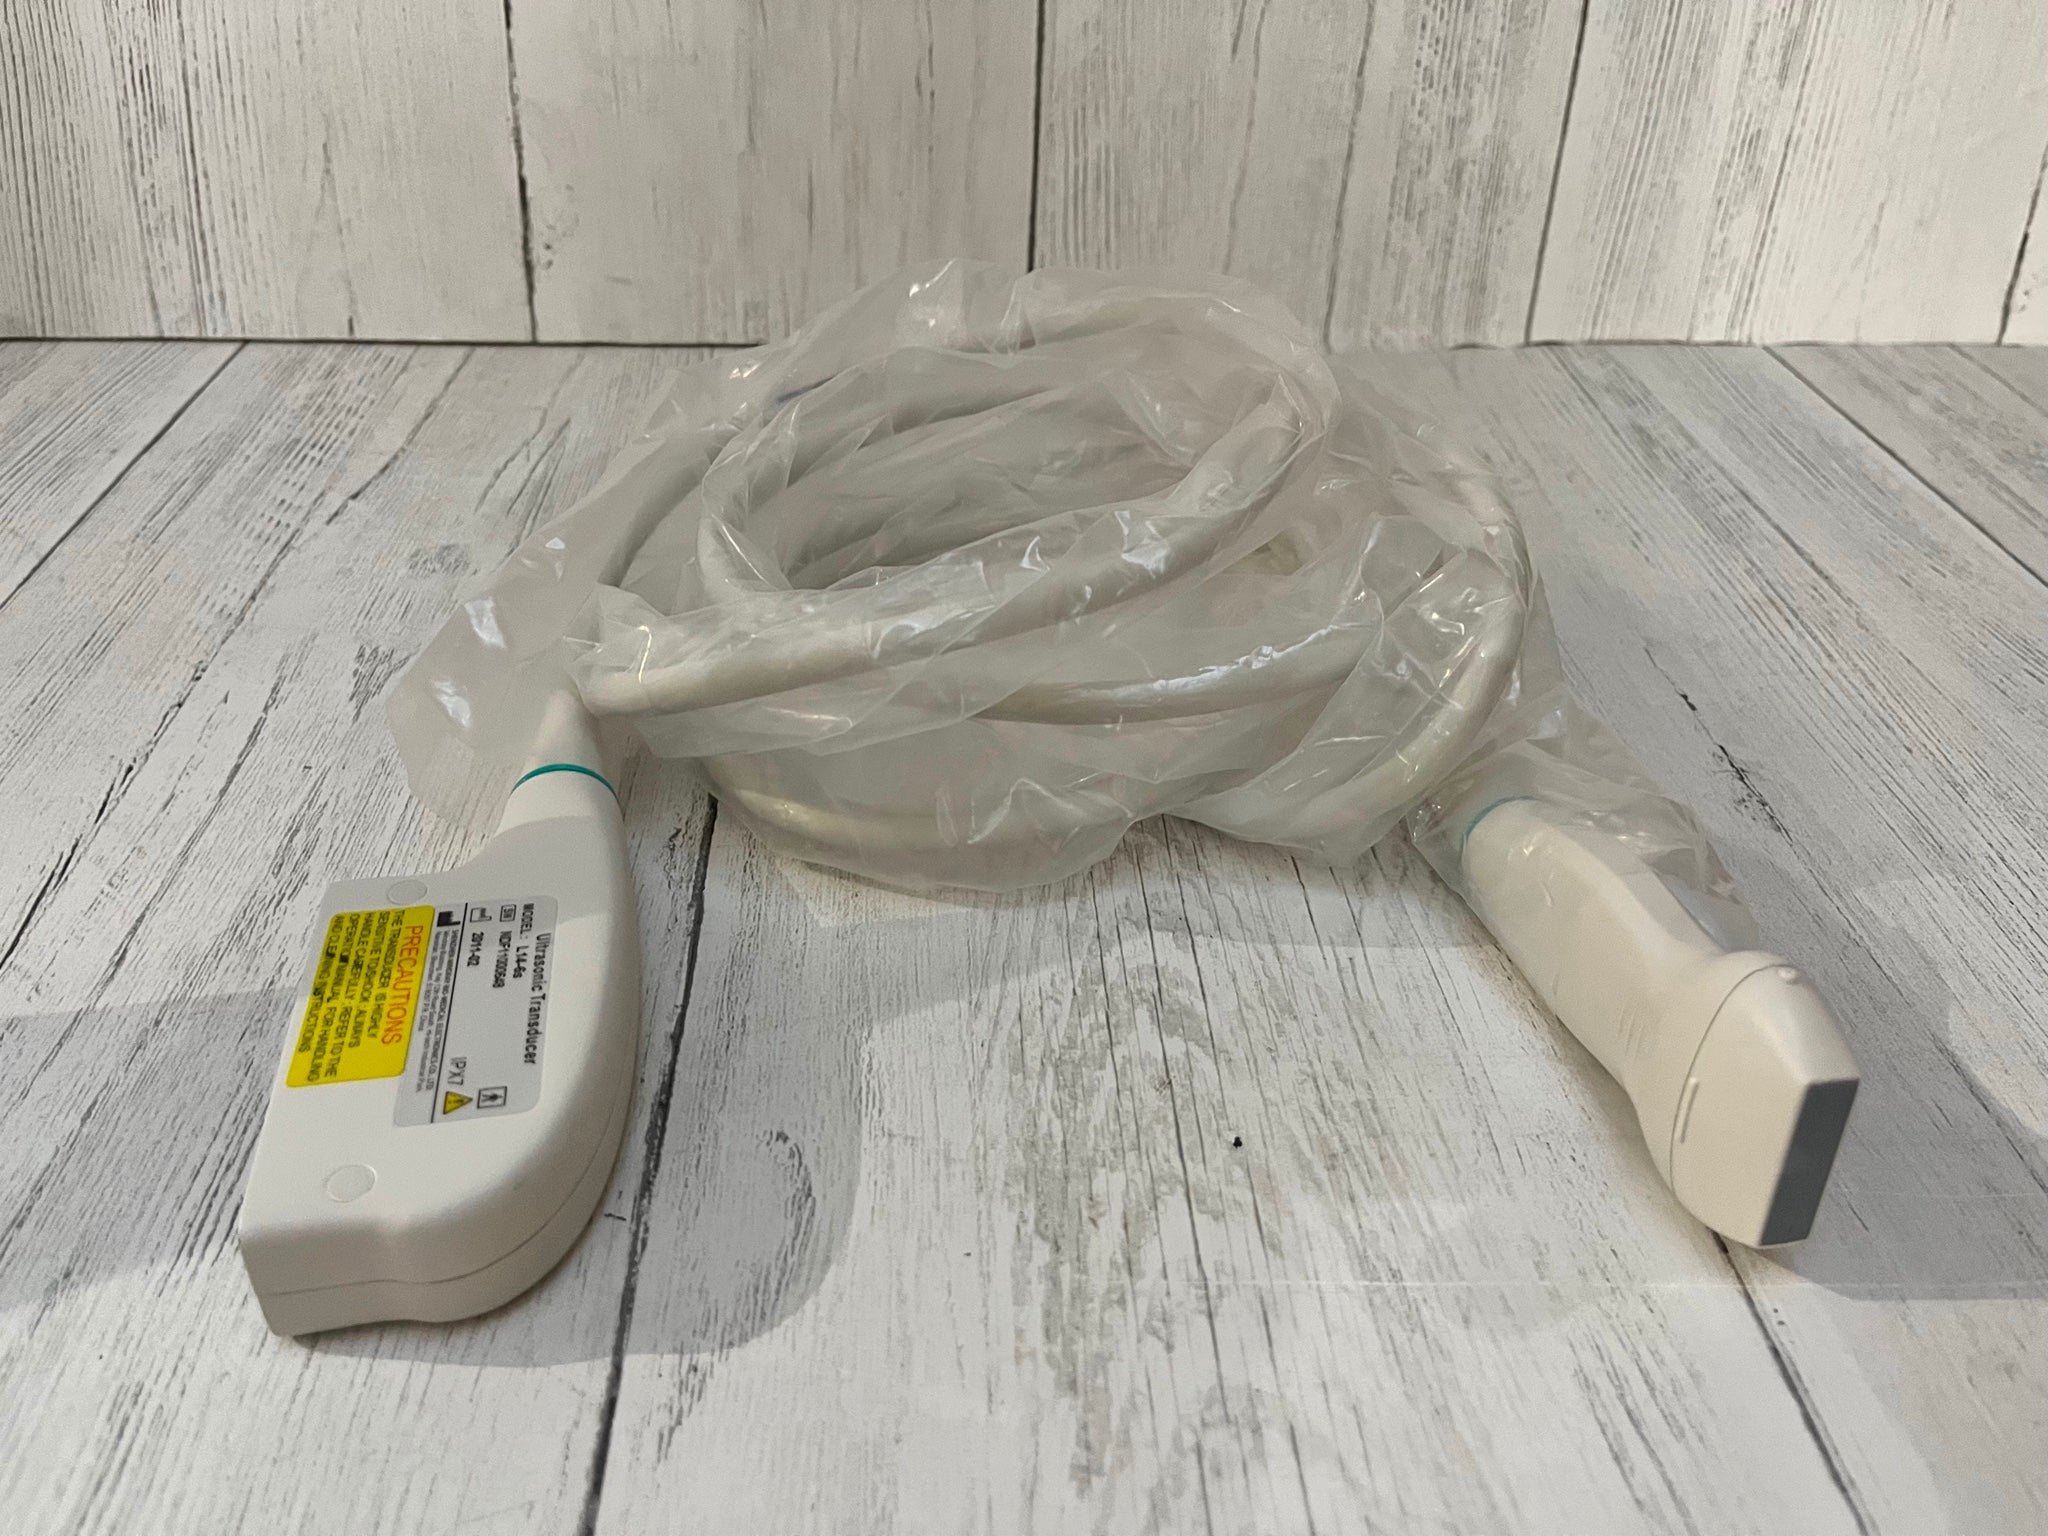

Condition:For parts or not working : An item that does not function as intended and is not fully operational. This includes items that are defective in ways that render them difficult to use, items that require service or repair, or items missing essential components. See the sellerâs listing for full details. See all condition definitions- opens in a new window or tab

Seller Notes:âTested using a Logiq P5 Ultrasound unit. Plugs into ultrasound and produces image. Image has dead zones and white bars inconsistent with other functional transducers (pictured). Show signs of use. Includes everything shown. Sold AS IS.â